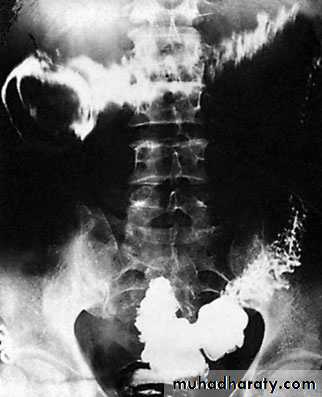

Barium enemaThe principal signs are :• loss of haustration, especially in the distal colon;• mucosal changes caused by granularity;• pseudopolyps;• in chronic cases, a narrow contracted colon.

Apple core appearance